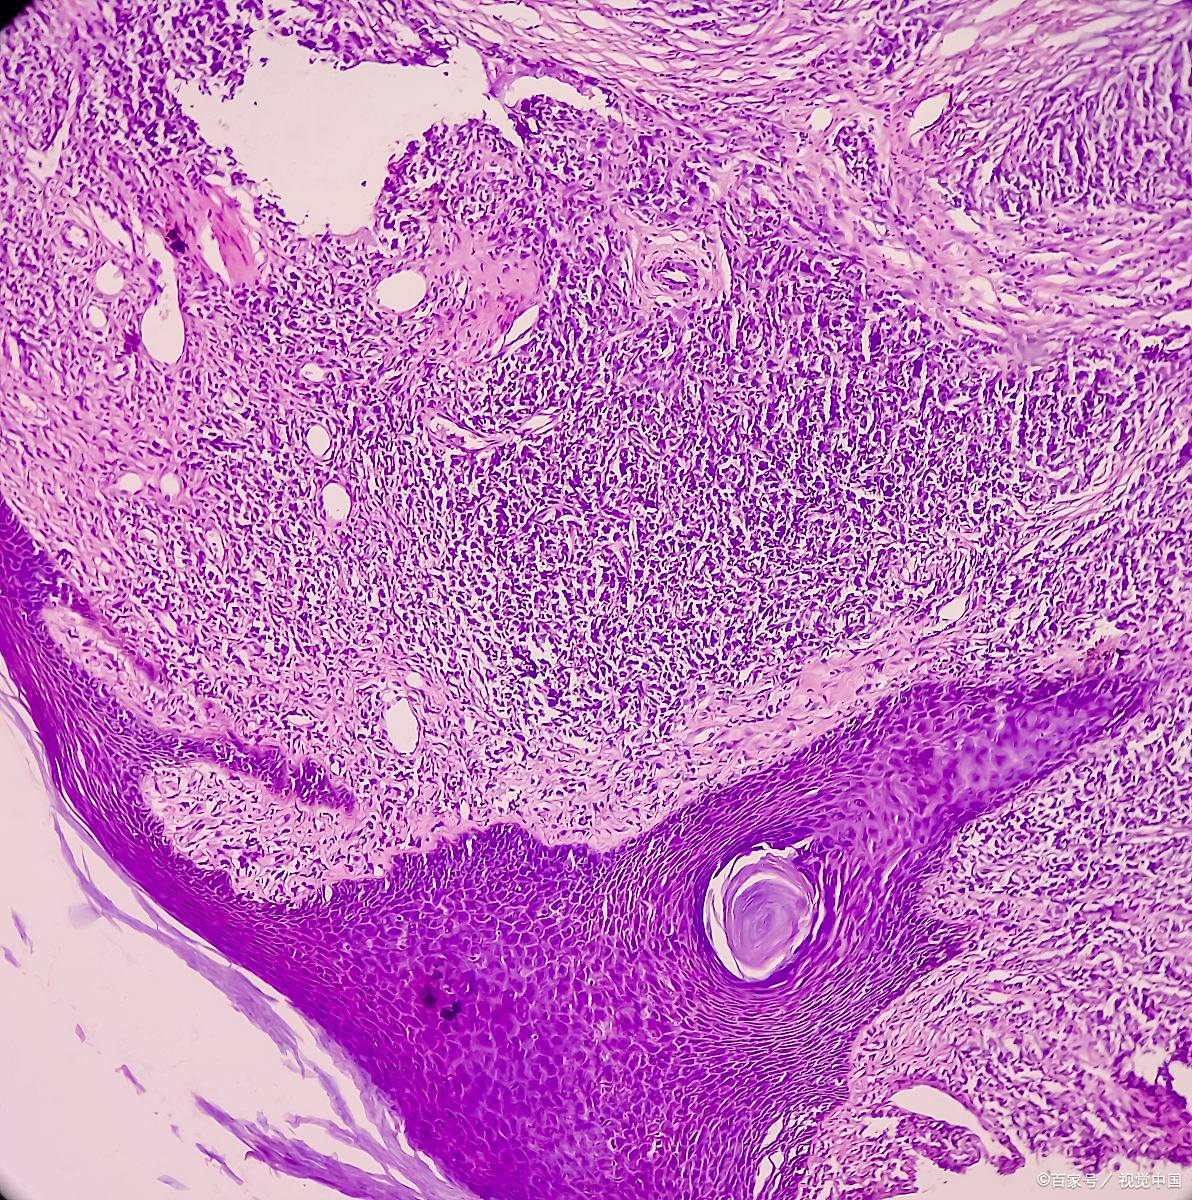

隆突性皮肤纤维肉瘤

图片尺寸2592x1944